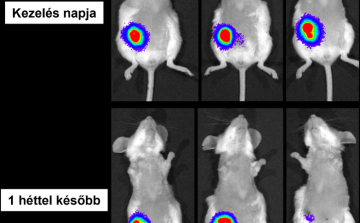

HUN-REN: új lendületet adhat a rák elleni harcnak a magyar kutatók fejlesztése